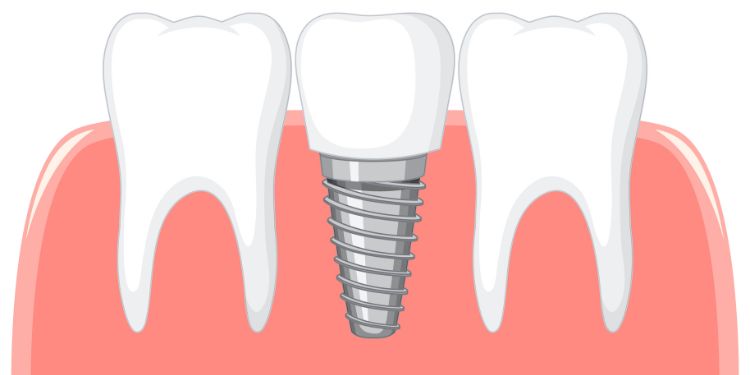

Innovations in Dental Implants and Dentistry

Journal of Dentistry And Oral Implants is an Open Access, Peer-Reviewed publication dedicated to disseminating cutting-edge scientific research in the areas of dental health, dental implantology, dental research, general dentistry, implant dentistry, and oral implants. Our journal is committed to providing a platform for the latest and most pertinent advancements in these fields.